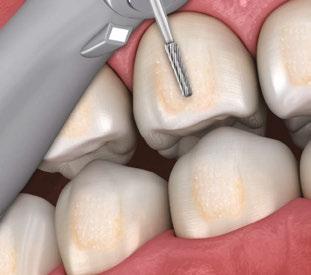

Bur and high-speed handpiece

In cases of extreme crowding, initial tooth reduction may be necessary using a bur in a high-speed handpiece before employing diamond strips. Fine-pointed diamonds and carbides are suitable for this purpose (Figures 10 and 11). This technique helps restore natural curvature and prevents the creation of an undesirable flat proximal surface. A flat proximal surface can create an illusion of continuous teeth, while a curved surface imparts a more natural appearance.